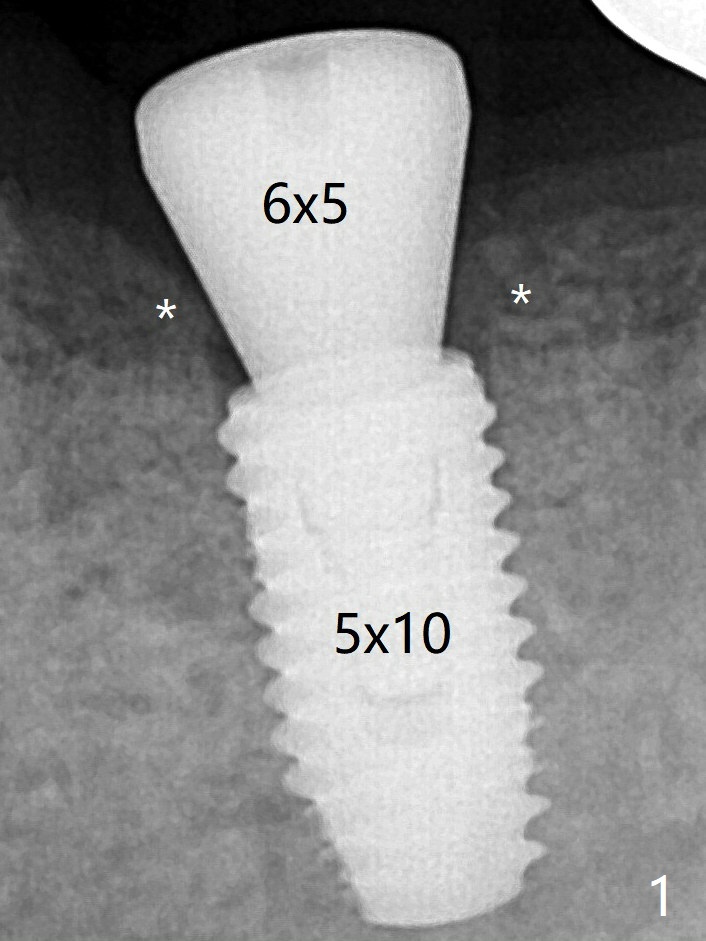

虽然愈合基台似乎完全就位,但是接近近中,远中牙槽嵴(图一:*),去除后,使用6毫米profile钻头,再次放置。术后病人没有任何不适。术后6.5月,基台完全就位,与没有牙槽嵴阻挡有关(图二)。骨质密度高,植入扭力高,没有造成骨质吸收。